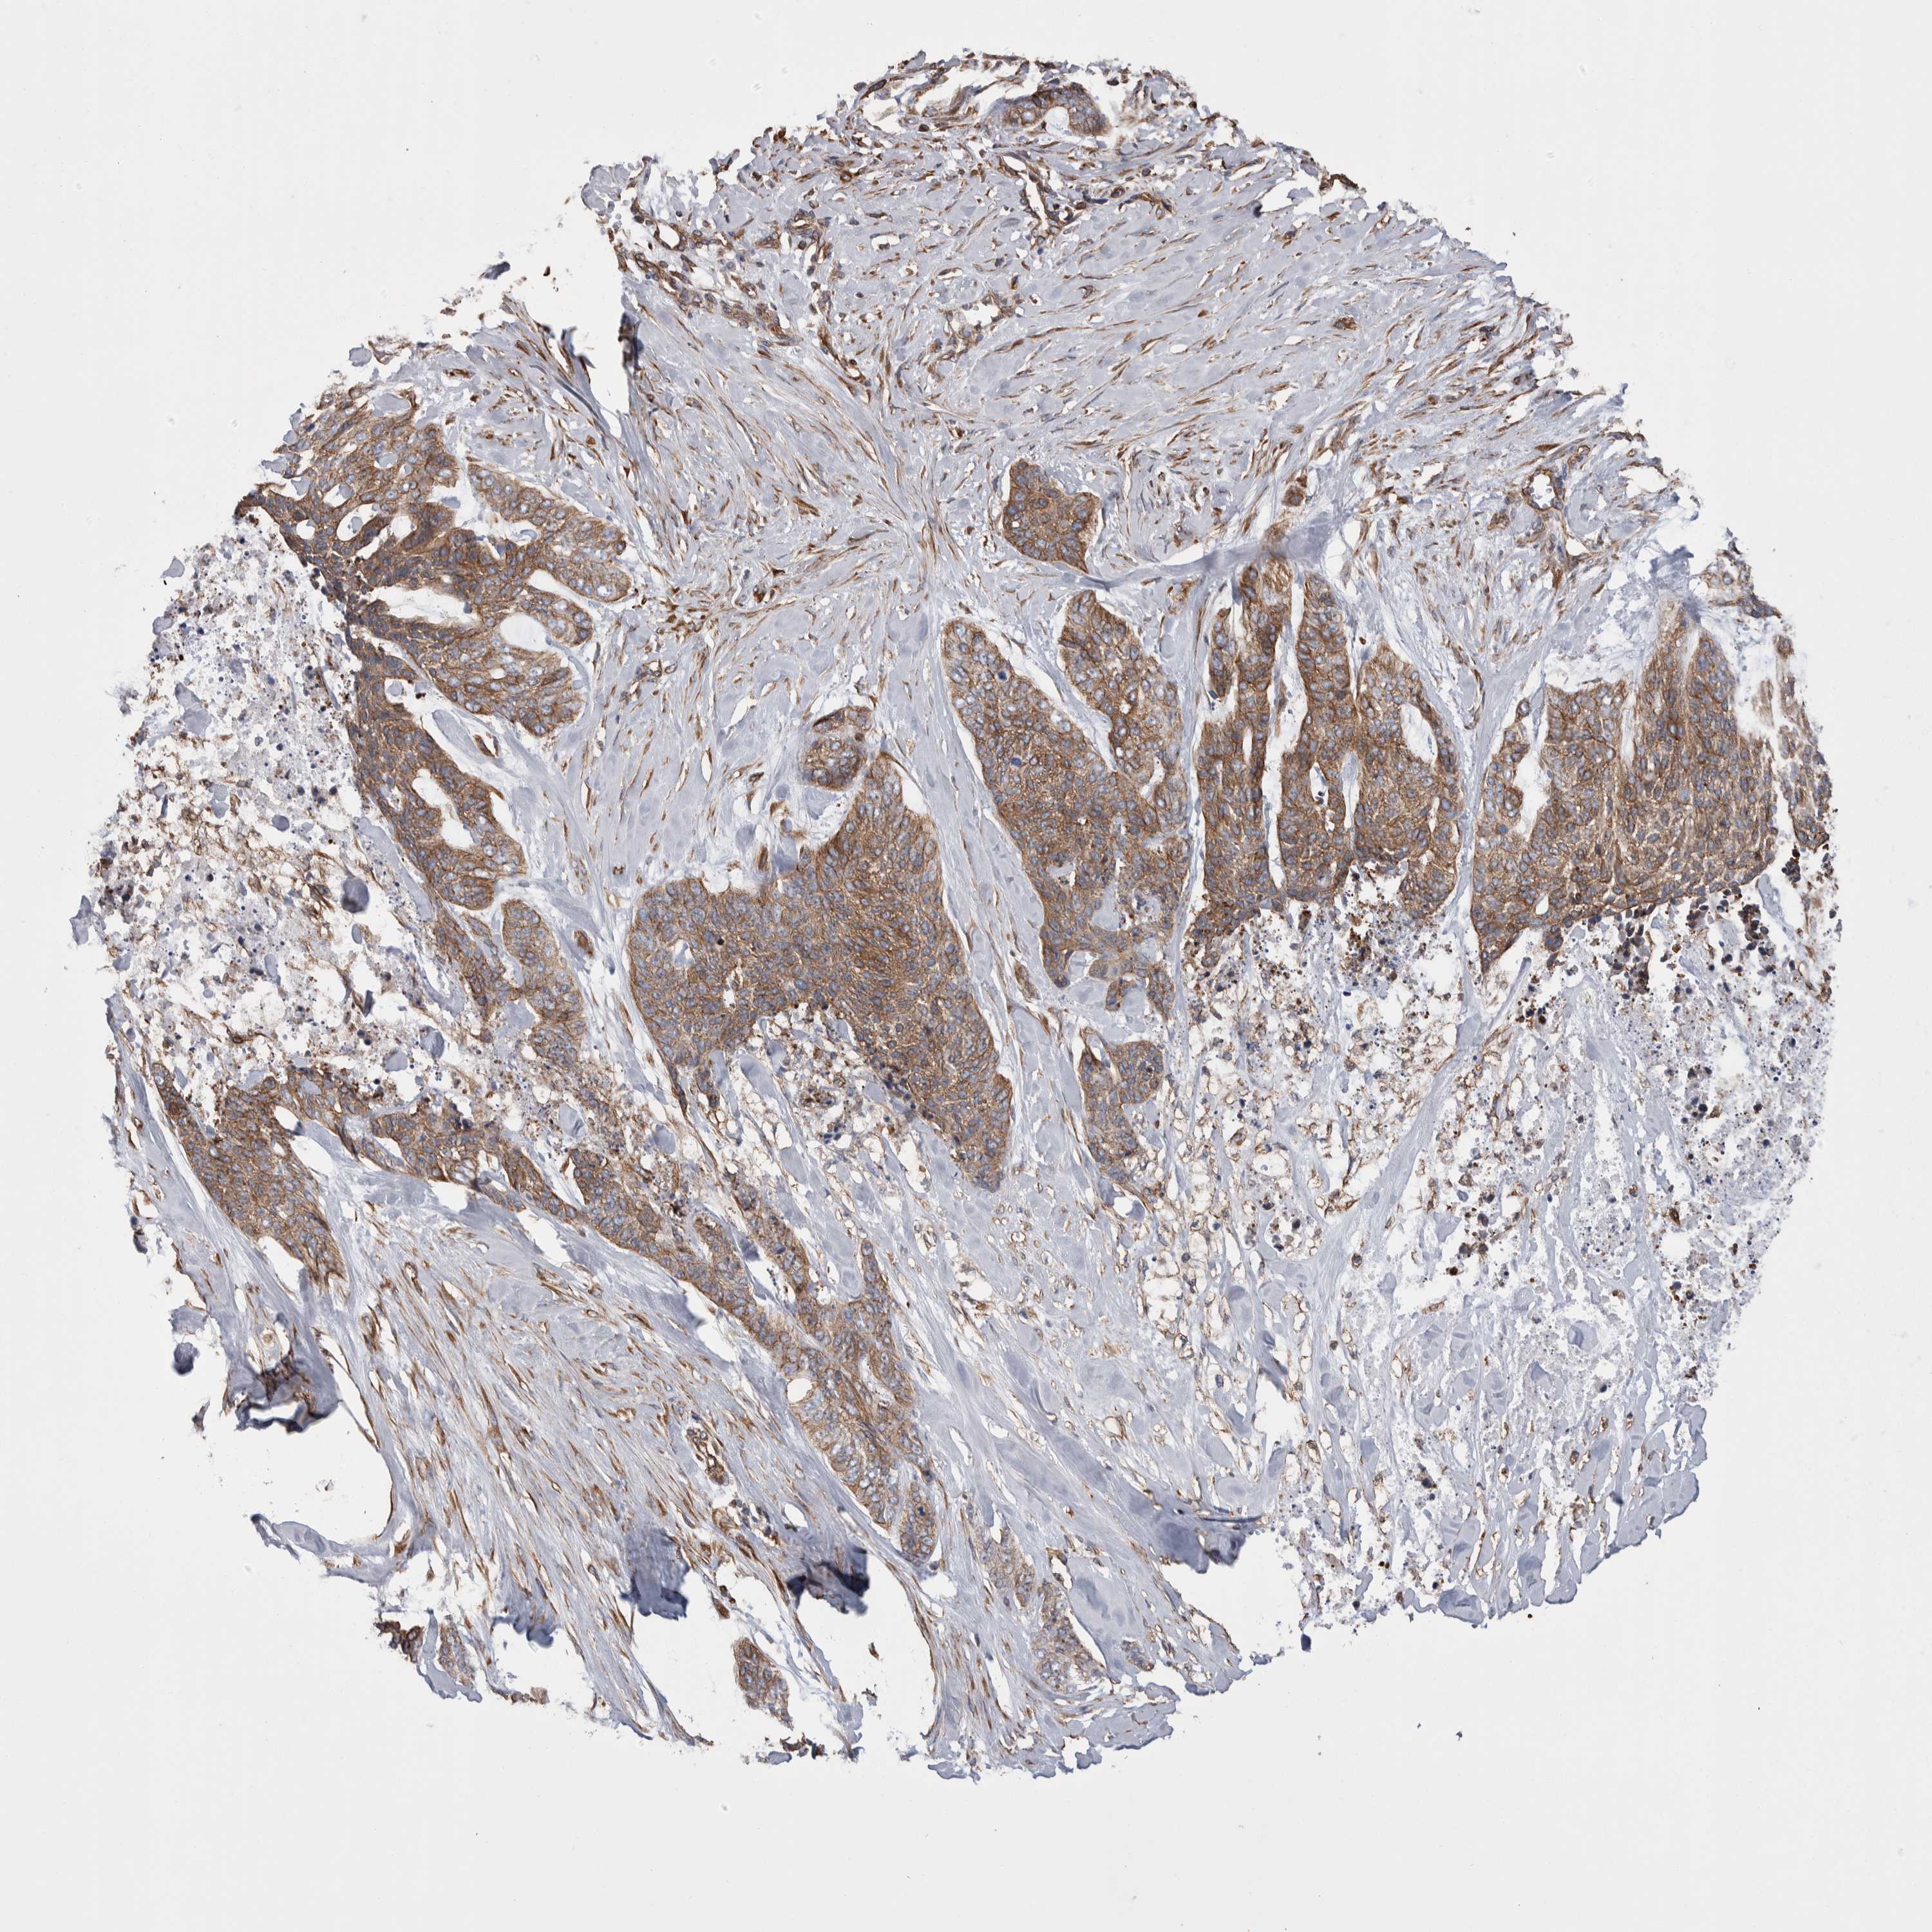

Basal cell and squamous cell cancer

SKIN CANCER - Protein expressioni

A mouse-over function shows sample information and annotation data. Click on an image to view it in a full screen mode. Samples can be filtered based on level of antibody staining by selecting one or several of the following categories: high, medium, low and not detected. The assay and annotation is described here.

Antibody stainingi

Antibody staining in the annotated cell types in the current human tissue is reported as not detected, low, medium, or high, based on conventional immunohistochemistry profiling in selected tissues. This score is based on the combination of the staining intensity and fraction of stained cells.

Each image is clickable and will lead to virtual microscopy that enables deeper exploration of all samples and also displays staining intensity scores, fraction scores and subcellular localization as well as patient and tissue information for each sample.

Antibody HPA020192

Antibody HPA024127

Staining

High

Medium

Low

Not detected

Intensity

Strong

Moderate

Weak

Negative

Quantity

>75%

75%-25%

<25%

None

Location

Nuclear

Cytoplasmic/membranous

Cytoplasmic/membranous,nuclear

Squamous cell carcinoma, NOS

Squamous cell carcinoma, metastatic, NOS